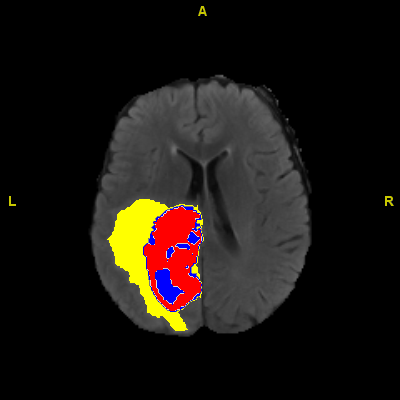

foto: Imagine medicală adnotată de AI care arată tumoră mărită, miez tumoral și regiuni de edem. Monash University